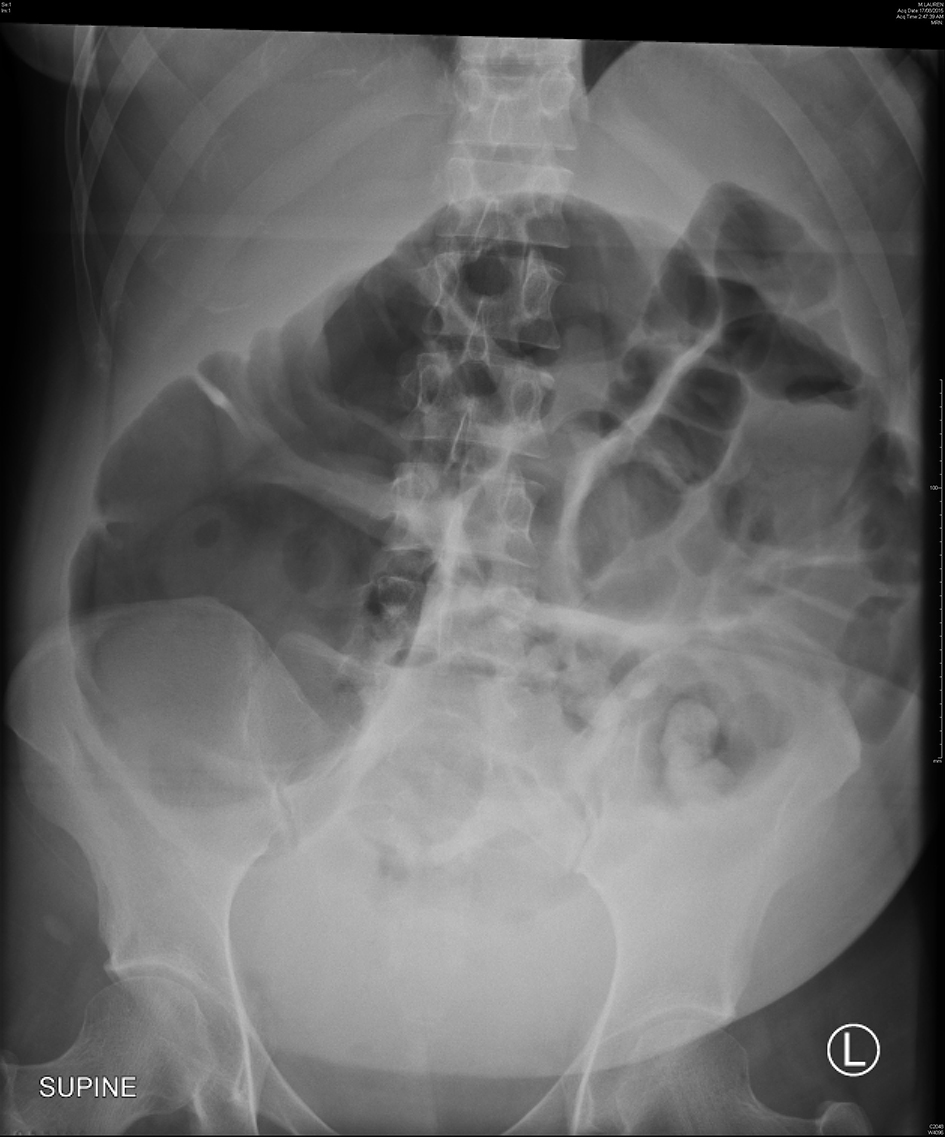

She represented on day 4 after cesarean section complaining of severe lower abdominal pain and worsening distension despite passing flatus and bowel motions. Physical examination revealed a grossly distended and peritonitic abdomen. Bowel sounds were audible although sluggish. Vital signs remained with normal range; however, she was febrile at 37.8 °C. Laboratory results showed an acute neutrophilia and C-reactive protein (CRP) of 120 mg/L. Abdominal X-rays revealed widespread colonic dilation with no free air (Fig. 1) and subsequent computed tomography (CT) scan confirmed a transition point within the distal colon. A provisional diagnosis of ACPO was made. An emergency diagnostic laparoscopy was performed and converted to laparotomy where necrotic cecum was found and a right hemi-colectomy with anastomosis was performed. The key histological features were focal transmural necrosis and incipient perforation, in keeping with the radiological suggestion of intestinal pseudo-obstruction. Her postoperative course was unremarkable and she was discharged day 6 after laparotomy.

![]() Click for large image | Figure 1. Abdominal X-ray of case 1 showing a dilated colon with the cecum measuring 12.5 cm in diameter. |